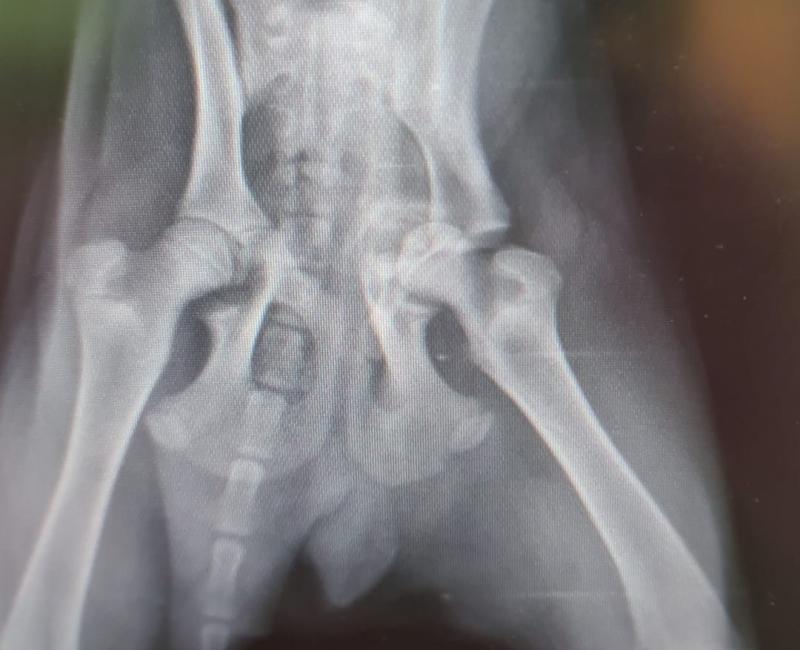

Sentimos muchísimo no haber podido salvarte. Pese a haber superado tu operación no ha servido de nada y la vida que te merecías nunca te llegará.